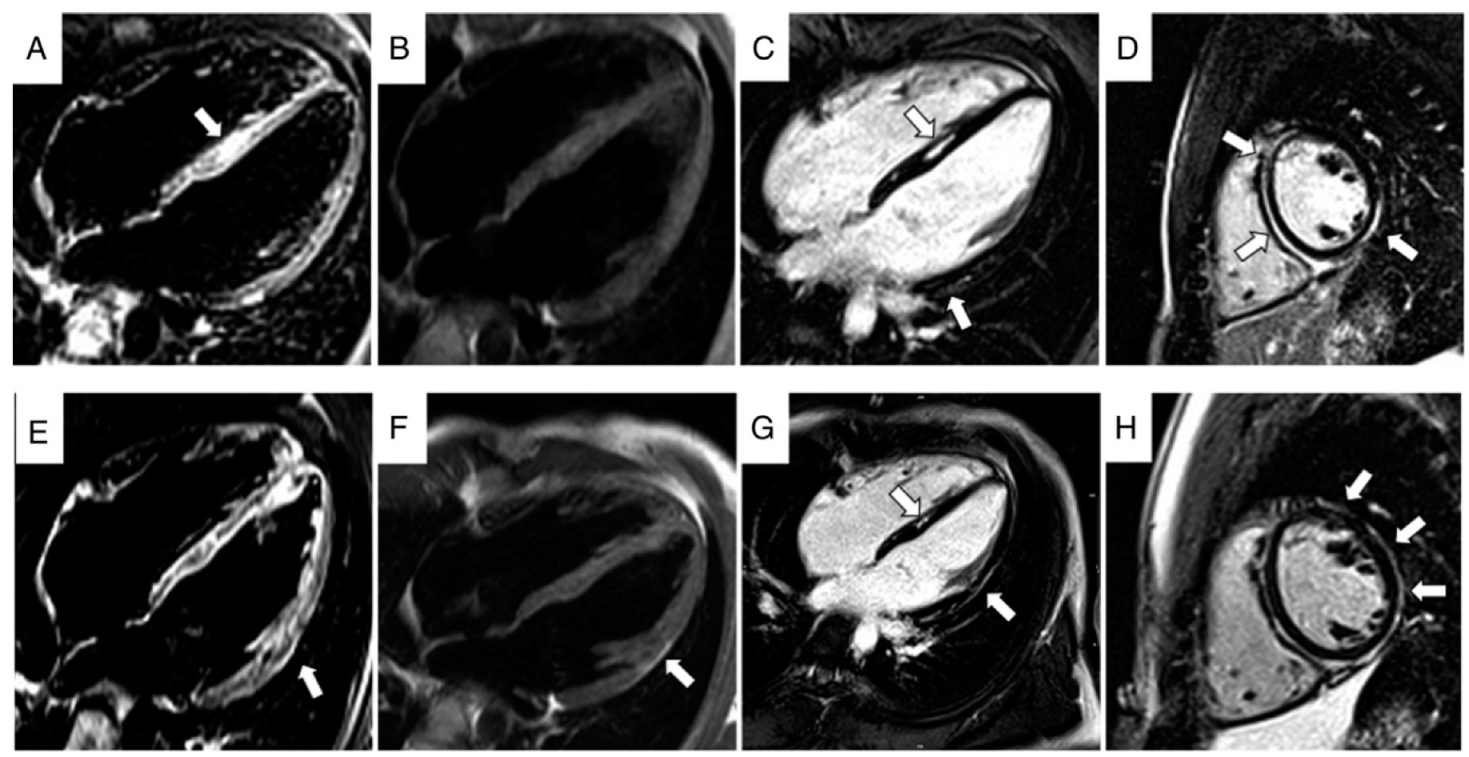

| Bariani, Europace 2021 [8] | -Aim: to evaluate the clinical features of patients affected by ACM presenting with chest pain and myocardial enzyme release in the setting of normal coronary arteries (‘hot-phase’) | -ACM patients presenting with chest pain and/or myocardial necrosis markers elevation in the setting of normal coronary arteries | -Among 530 patients fulfilling ARVC TFC, 23 (5%) experienced hot-phase episodes - Genetic testing was positive in 77% of cases and pathogenic -DSP was the most frequent involved gene - No patient complained of sustained ventricular arrhythmia or died suddenly during the hot-phase | 23 patients (12 M, mean age at symptoms 24 years, min 10–max 71 years) 5 ARVC, 9 BIV, 6 ALVC | DSP, DSG2, PKP2, DES | -Hot-phase represents an uncommon clinical presentation of ACM, which often occurs in pediatric patients and carriers of DSP gene mutations. Tissue characterization, family history, and genetic test represent fundamental diagnostic tools for differential diagnosis. |

| Bariani et al., Europace 2021 [8] | Chest pain and myocardial enzyme release in the setting of normal coronary arteries. Eleven patients underwent EMB patients which showed that myocarditis-like features, i.e., Foci of inflammatory infiltration associated with oedema and necrosis of the cardiomyocytes, were found in seven patients |